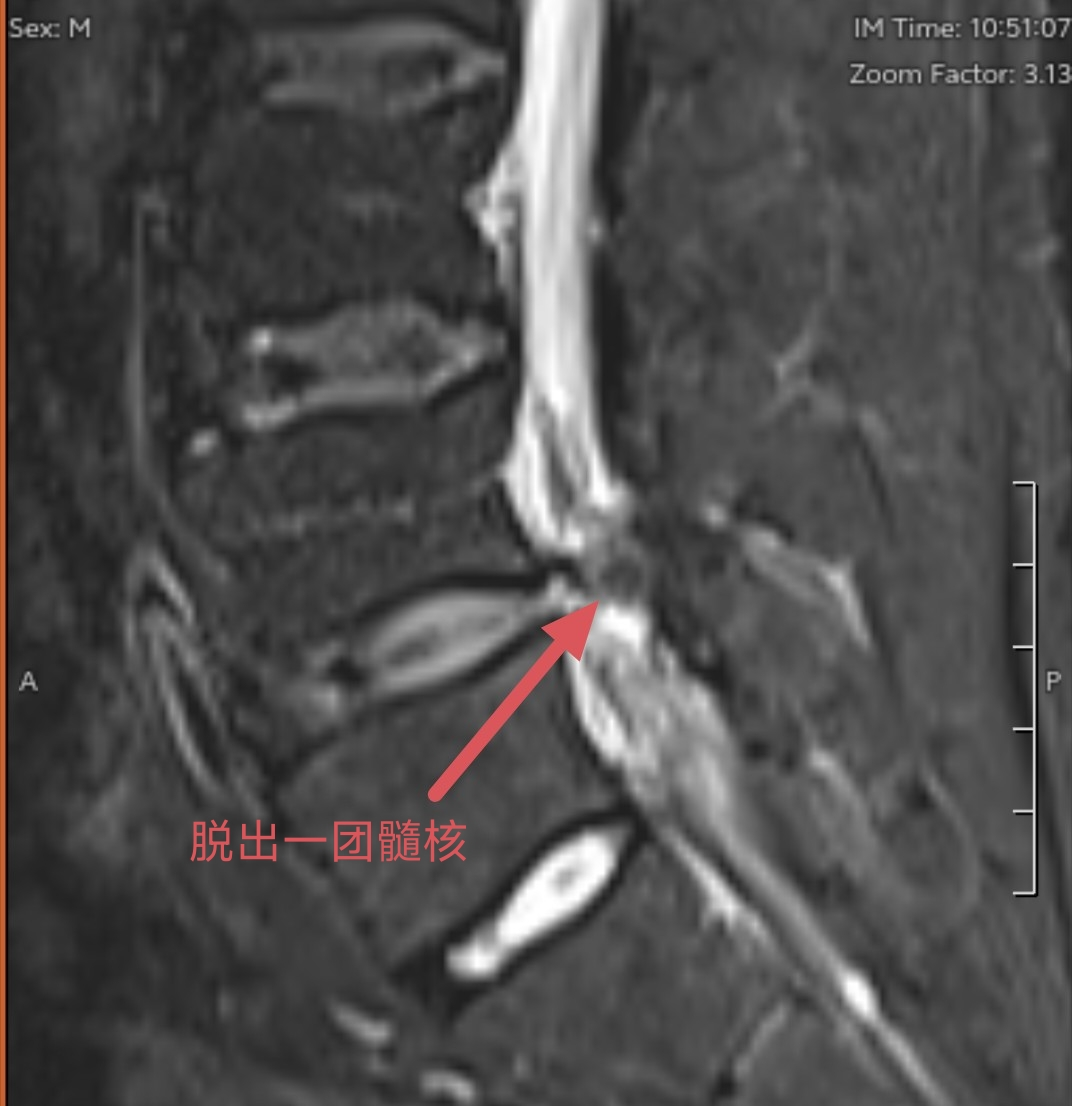

(CT影像下的腰椎间盘脱出所见)

(磁共振影像下的腰椎间盘脱出所见)

磁共振技术被誉为软组织的“透视眼”。磁共振利用水分子振动成像,对椎间盘、脊髓、神经根、韧带等含水量高的软组织具有极高的分辨率。在磁共振图像上,医生可以清晰地看到突出的椎间盘究竟在哪个位置、压迫了哪一根神经根、压迫的程度是轻度接触还是重度挤压,甚至能观察到神经本身是否出现了水肿或变性。